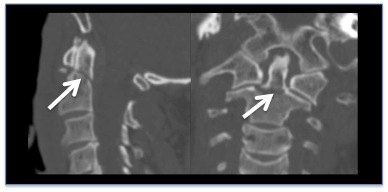

- TC de alta resolução da coluna cervical

- TC da coluna vertebral inteira